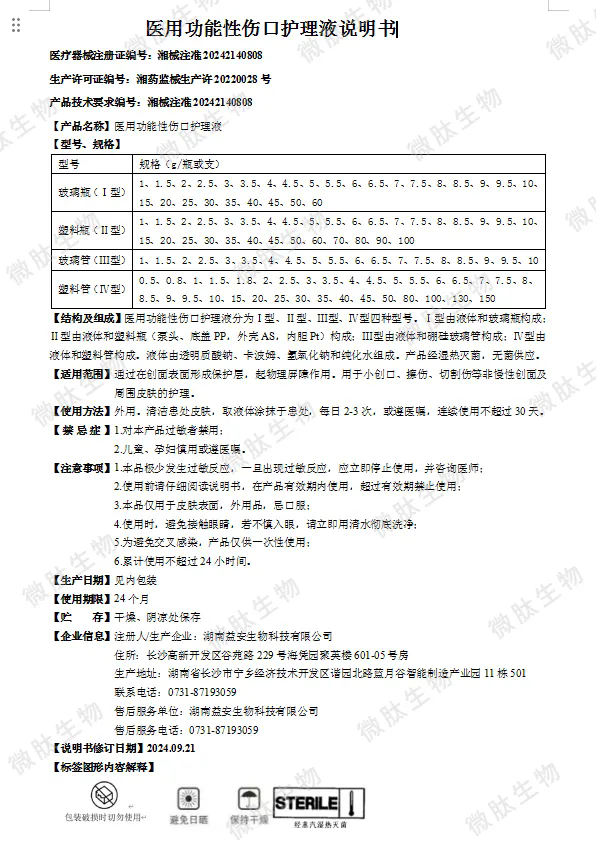

3. 产品质量与安全: 国家药品监督管理局对医疗器械产品注册证的审评过程极为严格,需经过多轮专家评审和临床试验验证,以确保产品的有效性。湖南微肽生物的“医用功能性伤口护理液”凭借其卓越的产品性能和严格的质量控制体系,成功通过了国家药品监督管理局的审评。

促进伤口愈合:产品含有多种有助于伤口愈合的活性成分,能够刺激细胞再生,加速伤口组织的修复过程,缩短伤口愈合时间。

减少疤痕形成:通过调节伤口部位的微环境,护理液能够有效减少疤痕组织的过度增生,降低疤痕形成的可能性。

抗菌消炎:产品中添加了具有抗菌消炎作用的成分,能够有效杀灭或抑制伤口表面的细菌、病毒等微生物,防止感染的发生。

保持伤口湿润:具有良好的保湿性能,能够在伤口表面形成一层保护膜,保持伤口部位的湿润度,有助于减轻患者的疼痛感和不适感。

易于吸收和使用:产品设计人性化,使用方便快捷。其质地清爽、不粘腻,易于被伤口吸收。

8. 质量与安全:产品经过严格的质量控制和安全检测,确保每一瓶护理液都能达到高标准的质量要求。